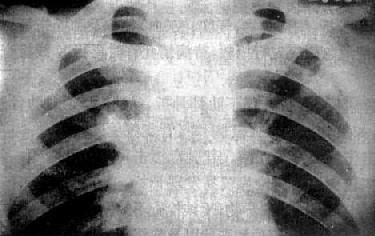

左肺浸润型肺结核空洞形成

图3-1-24 左肺浸润型肺结核空洞形成

左肺上野第2前肋间边缘模糊的致密影,其中可见空洞